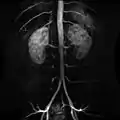

In human anatomy, the abdominal aorta is the largest artery in the abdominal cavity. As part of the aorta, it is a direct continuation of the descending aorta (of the thorax).[1]

The abdominal aorta begins at the level of the diaphragm, crossing it via the aortic hiatus, technically behind the diaphragm, at the vertebral level of T12.[1] It travels down the posterior wall of the abdomen, anterior to the vertebral column. It thus follows the curvature of the lumbar vertebrae, that is, convex anteriorly. The peak of this convexity is at the level of the third lumbar vertebra (L3). It runs parallel to the inferior vena cava, which is located just to the right of the abdominal aorta, and becomes smaller in diameter as it gives off branches. This is thought to be due to the large size of its principal branches. At the 11th rib, the diameter is 122mm long and 55mm wide and this is because of the constant pressure.[2] The abdominal aorta is clinically divided into 2 segments:

1. The suprarenal abdominal or paravisceral segment, inferior to the diaphragm but superior to the renal arteries.

2. The Infrarenal segment, inferior to the renal arteries and superior to the iliac bifurcation.